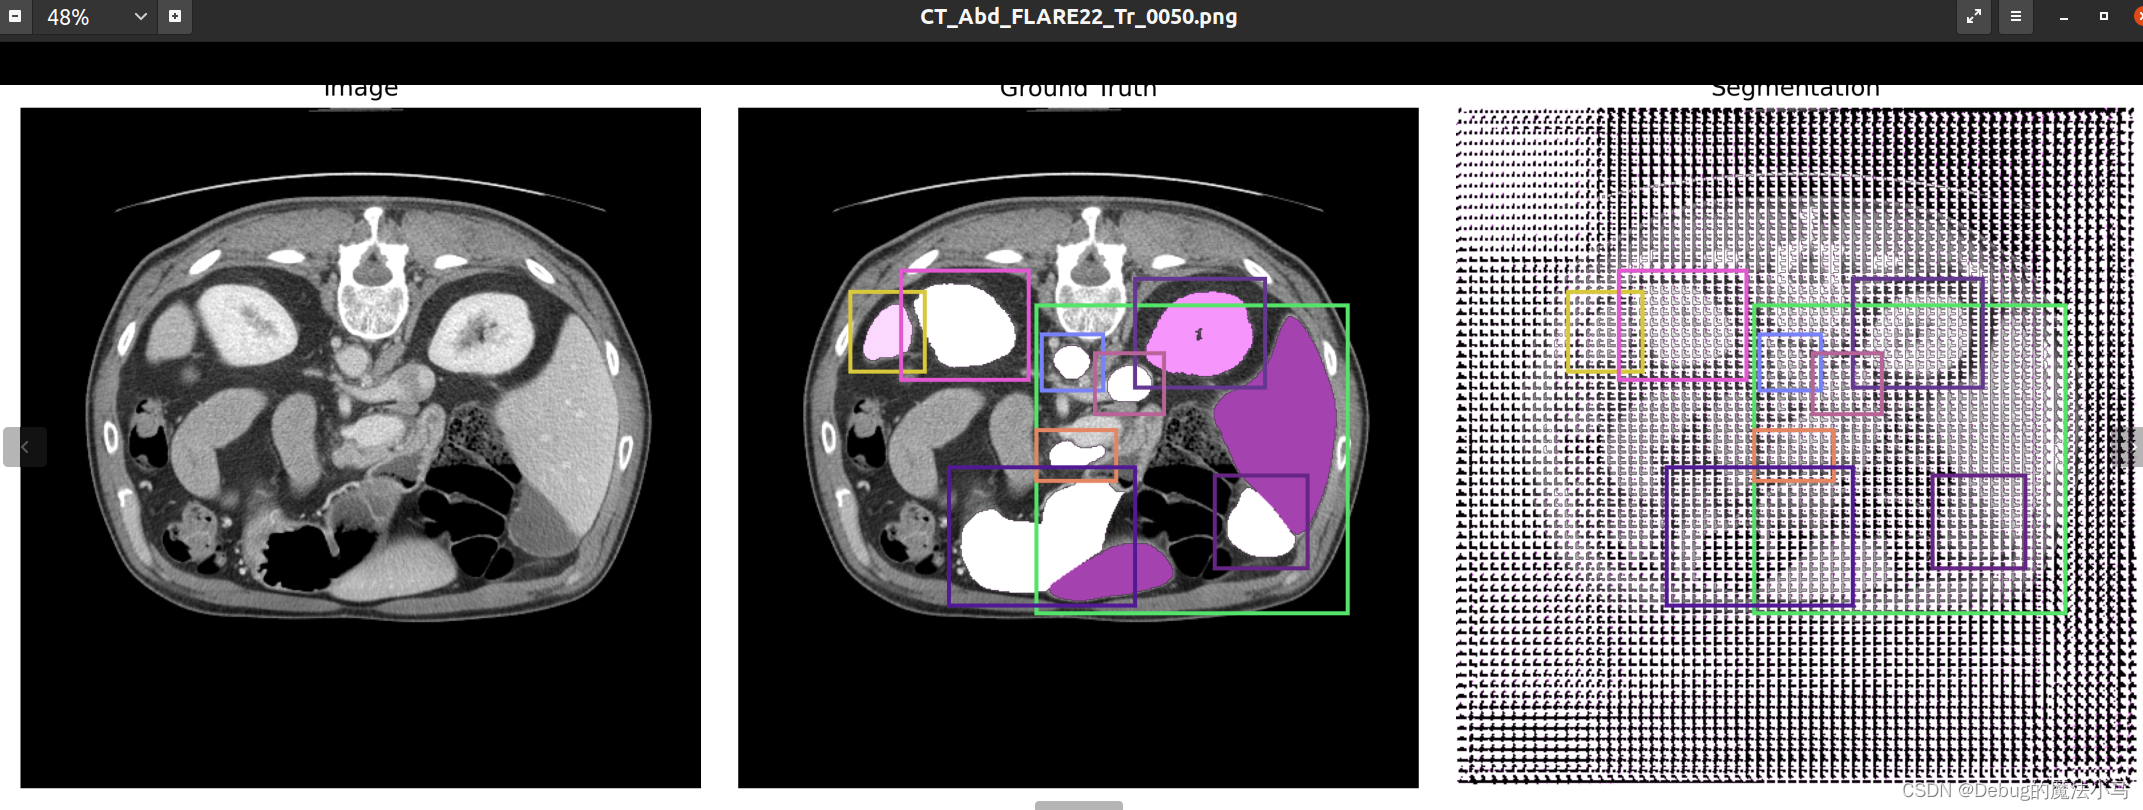

这是之前的结果图:

我把save_overlay参数设为True,运行后:

似乎没啥问题。暂时先这样了。